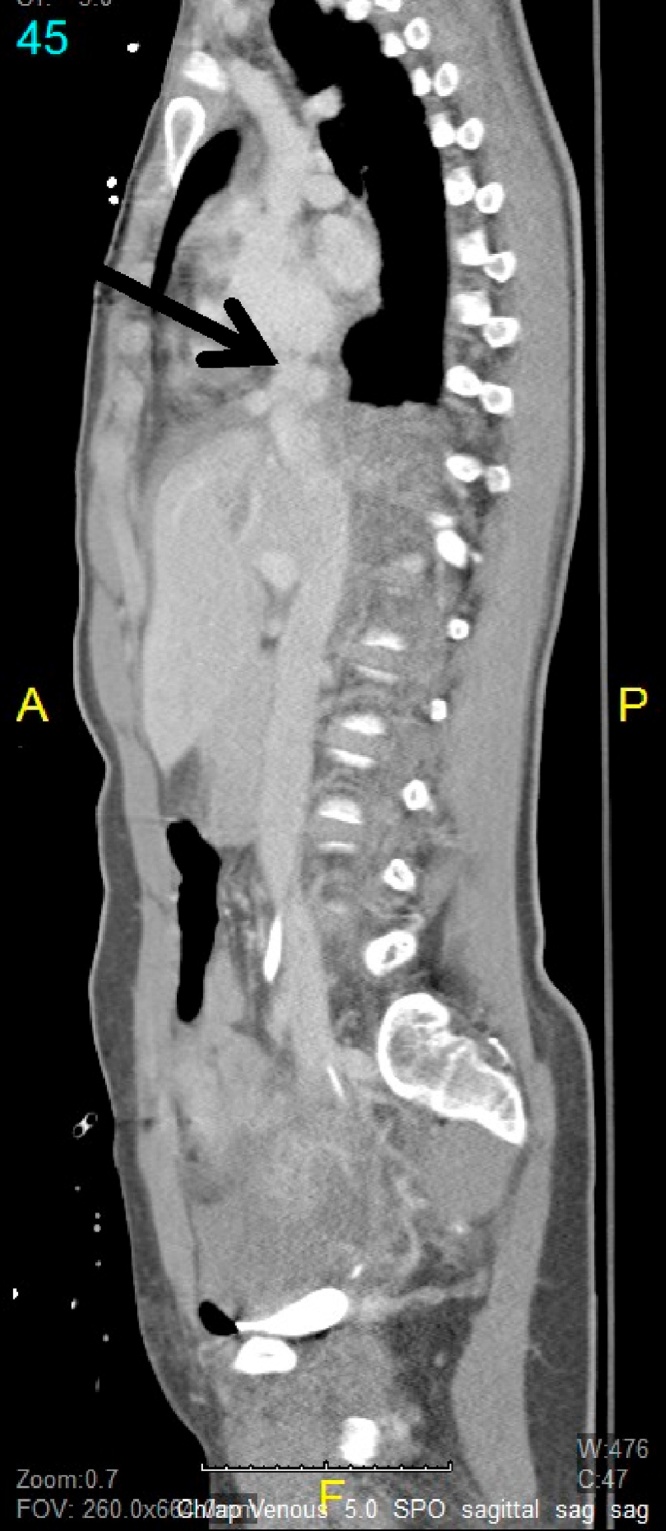

She was transferred out of the surgical intensive care unit (SICU). A repeat CT venogram on HD 9, 14 (Fig. 2), and 21 after injury demonstrated stability of the IVC pseudoaneurysms. Owing to her continued hemodynamic stability and the lack of pseudoaneurysm growth, a nonoperative approach was maintained, with planned CT venogram 4 weeks later. The repeat CT scan showed a decrease in size of the IVC pseudoaneurysm from 1.5 to _1 cm. After this decrease in size, it was decided to perform repeat imaging in 6 months with a plan for surgical intervention only in the presence of clinical symptoms or enlargement. She was subsequently discharged to home after a 26-day hospital stay. A repeat abdominal CT, obtained 6 month (Fig. 3) later, demonstrated resolution of IVC pseudoaneurysms.

Fig. 2.

A sagittal image from the patient’s repeat computed tomography study demonstrates stable pseudoaneurysm along the confluence of the suprahepatic inferior vena cava (IVC).